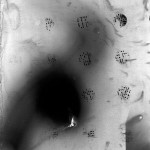

ANALOG PHOTOGRAPHY WITHOUT CAMERA_PHOTOGRAMS

// The Alzheimer disease moves itself slowly, silently, almost unnoticed. As a mold it expands within the Brain. Bit by bit, invisible, creeping, it conquers and controls the body and soul of many human beings. The Book “Demens” is the attempt to effectively communicate what Alzheimer causes. The visualization is composed by emotional abstract pictures, practical information as well as diagnostics tests and quotes from several Alzheimer patients.

// Die Alzheimer-Krankheit bewegt sich anfangs leise, fast unbemerkt. Wie ein Schimmel breitet sie sich im Gehirn aus. Stück für Stück, still, schleichend, aber zielstrebig erobert und steuert sie den Körper und Geist vieler Menschen. Das Buch »Demens« verkörpert den Versuch, die Alzheimer Krankheit objektiv, ausführlich und verständlich zu vermitteln. Zur Visualisierung dieser Krankheit werden emotionale und abstrakte Bilder, objektive und praktische Informationen sowie aus¬gewählte Diagnose-Verfahren und Zitate einiger Alzheimerkranker zusammengefügt.